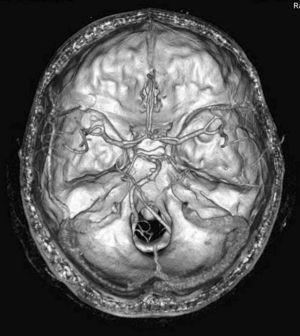

Figura 2. Reconstrucción 3D en la que se observa flujo en la arteria carótida común y arterias vertebrales extracraneales, así como en las diversas ramas de la arteria carótida externa. Nótese el afilamiento de la arteria carótida interna (flecha gruesa). En el análisis de flujo de los vasos visualizados (marcado mediante línea puntos suspensivos en color blanco) se observa la desviación del flujo de la carótida primitiva hacia la carótida externa.

Figura 5. Reconstrucción 3D de una angio-tomografía computarizada cerebral en un paciente con flujo sanguíneo cerebral. Se identifica perfectamente el polígono de Willis, ambas arterias carótidas internas y sus diferentes ramas, así como la circulación posterior con arterias vertebrales y arteria basilar.